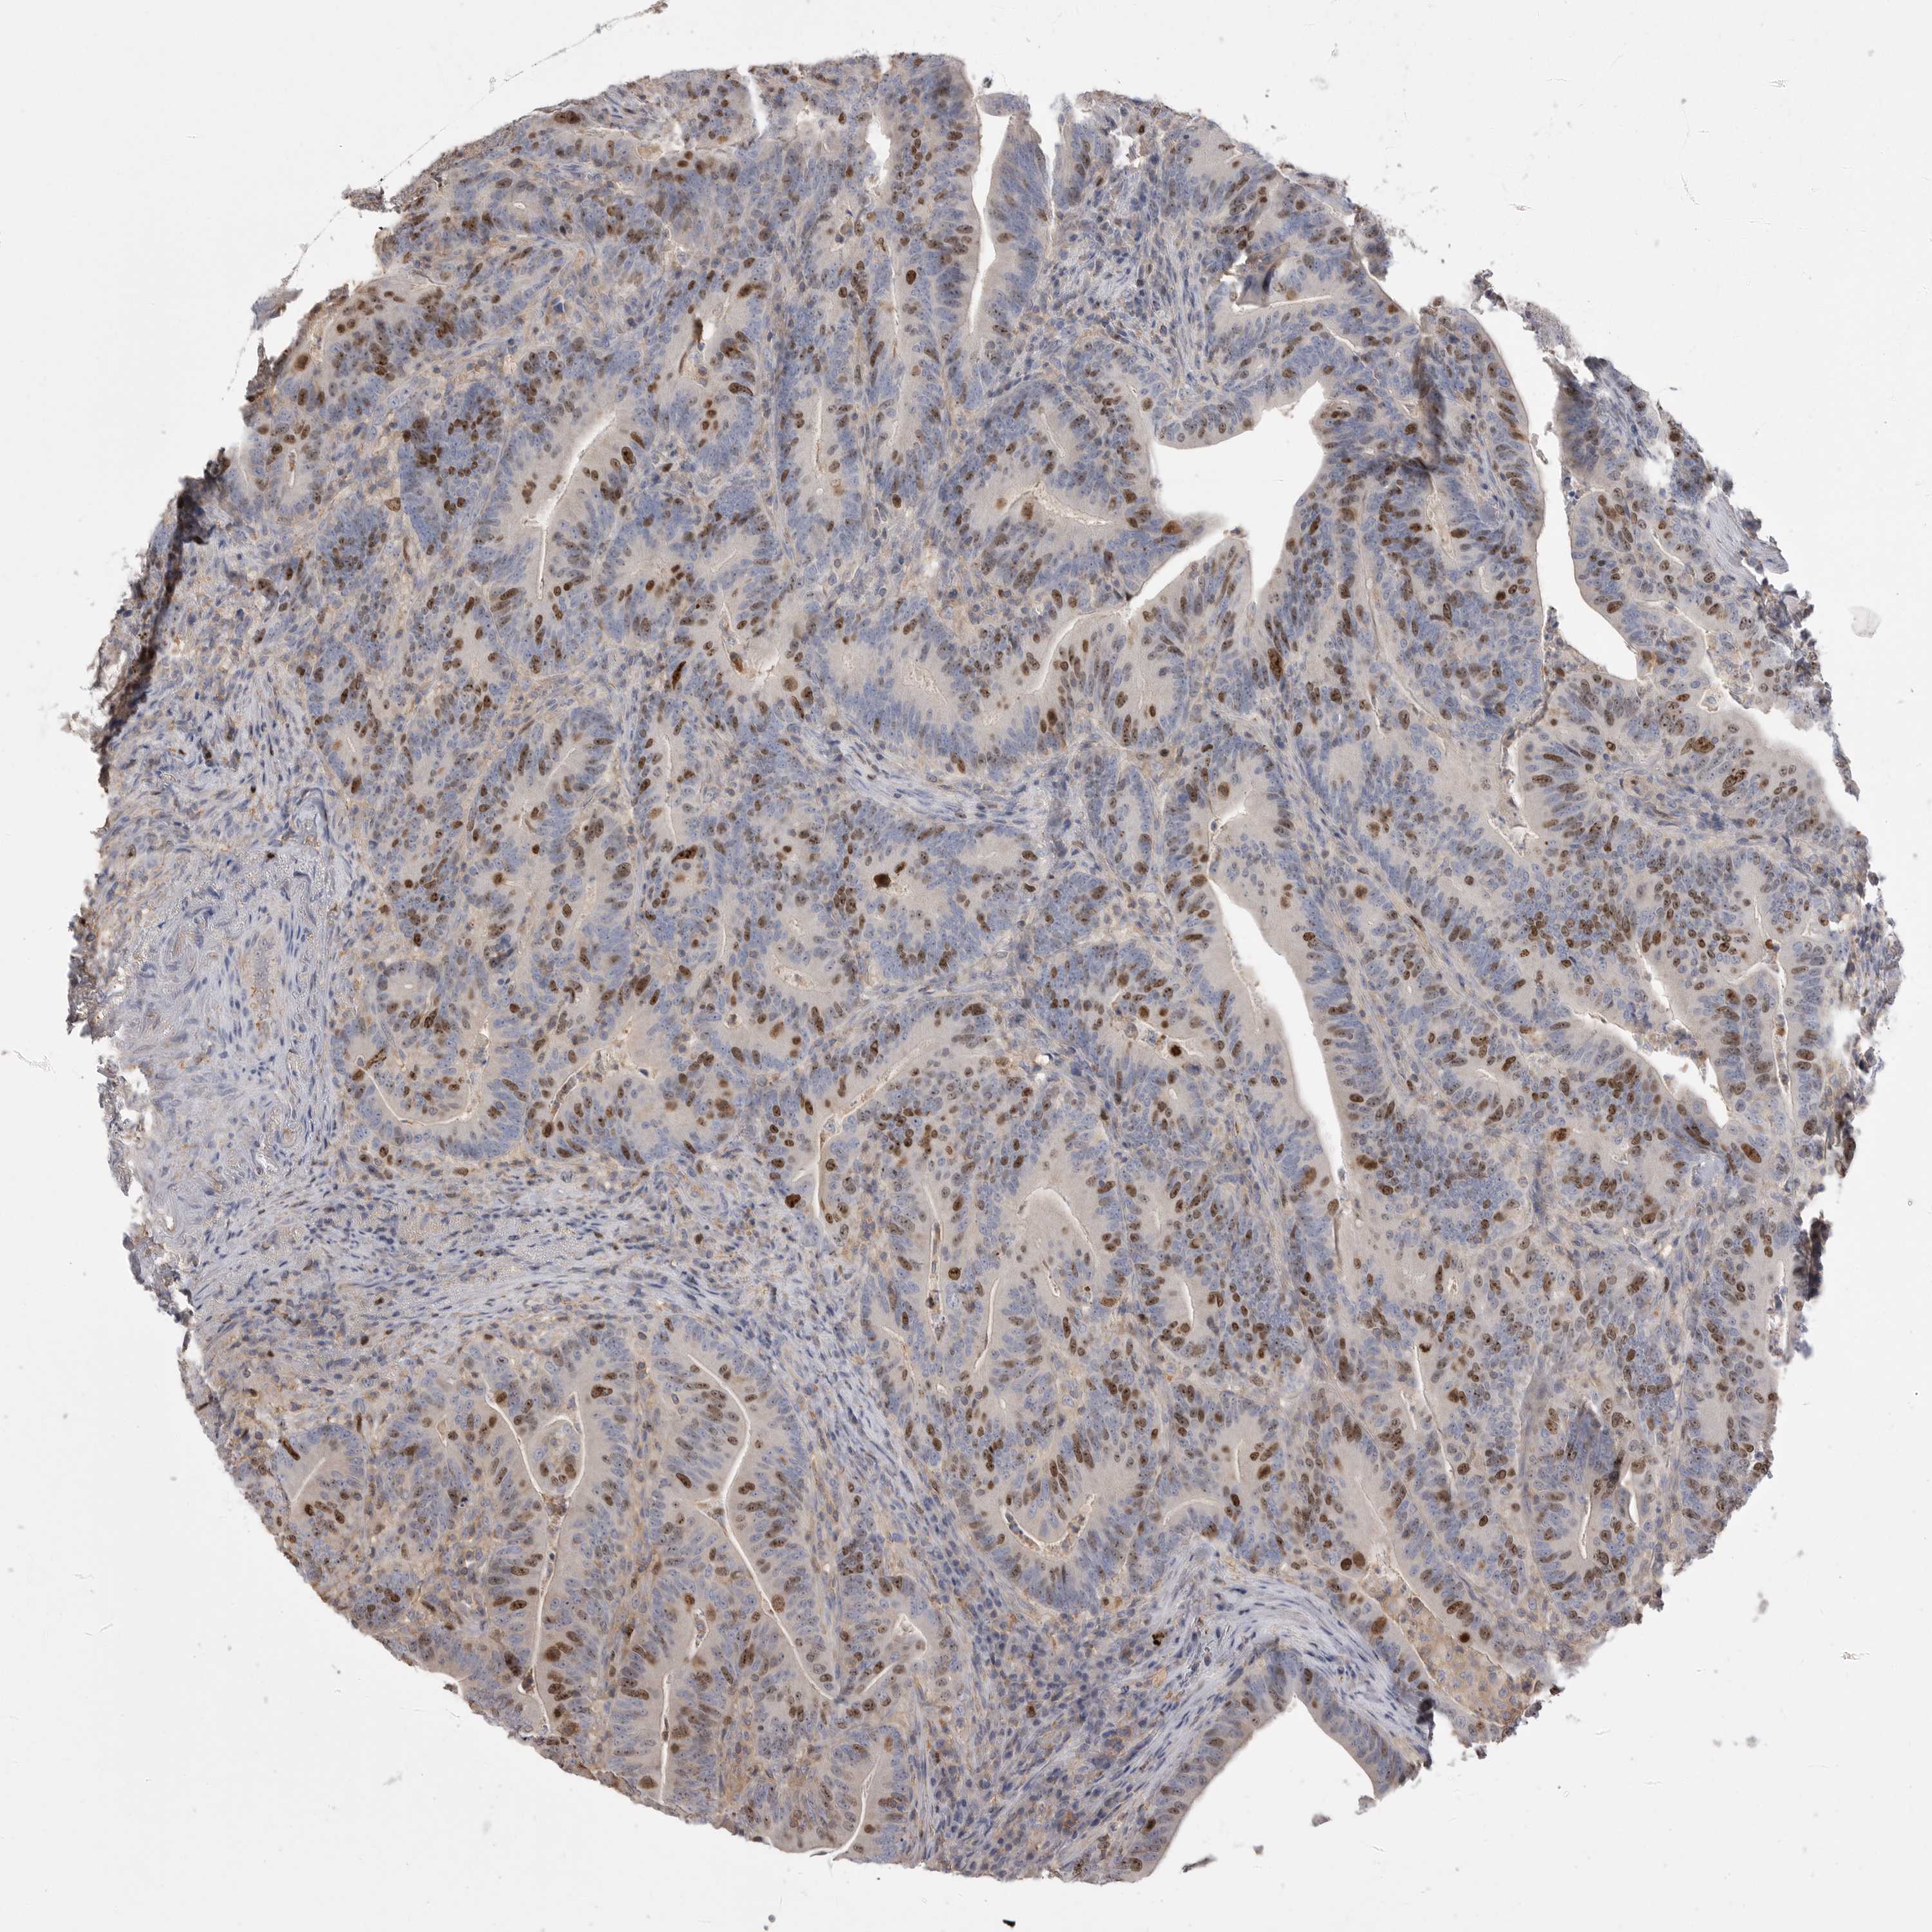

CANCER COLORECTAL CANCER Show tissue menu

Colorectal cancer

Human cancer

Colon adenocarcinoma